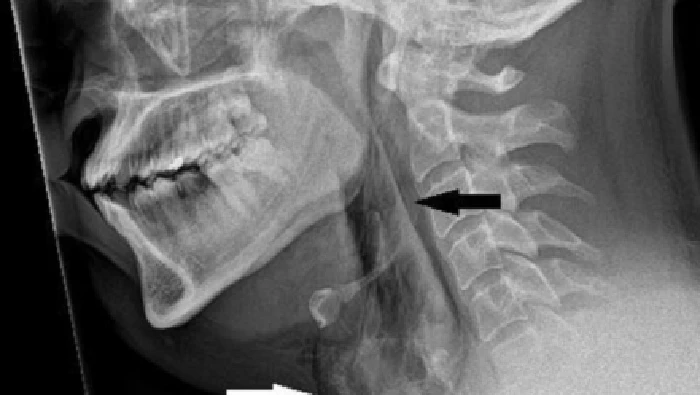

Pria itu dilarikan ke Ninewells Hospital di Dundee karena merasakan nyeri hebat setelah menahan bersin. Hasil pemeriksaan CT scan menemukan adanya sobekan kecil berukuran 2 mm pada bagian tenggorokannya.

Kasus ini dicatat dalam jurnal medis BMJ Case Reports. Ketika diperiksa, dokter mendengar suara seperti retakan saat memegang leher pasien dan menemukan bahwa ia mengalami kesulitan mengendalikan gerakan leher. Pria itu mengalami kejadian tersebut saat sedang mengemudi.

Robekan seperti spontaneous tracheal perforation merupakan kondisi langka namun berpotensi mengancam jiwa. Kasus serupa juga pernah dilaporkan, termasuk pada seorang pria di Leicester pada tahun 2018.